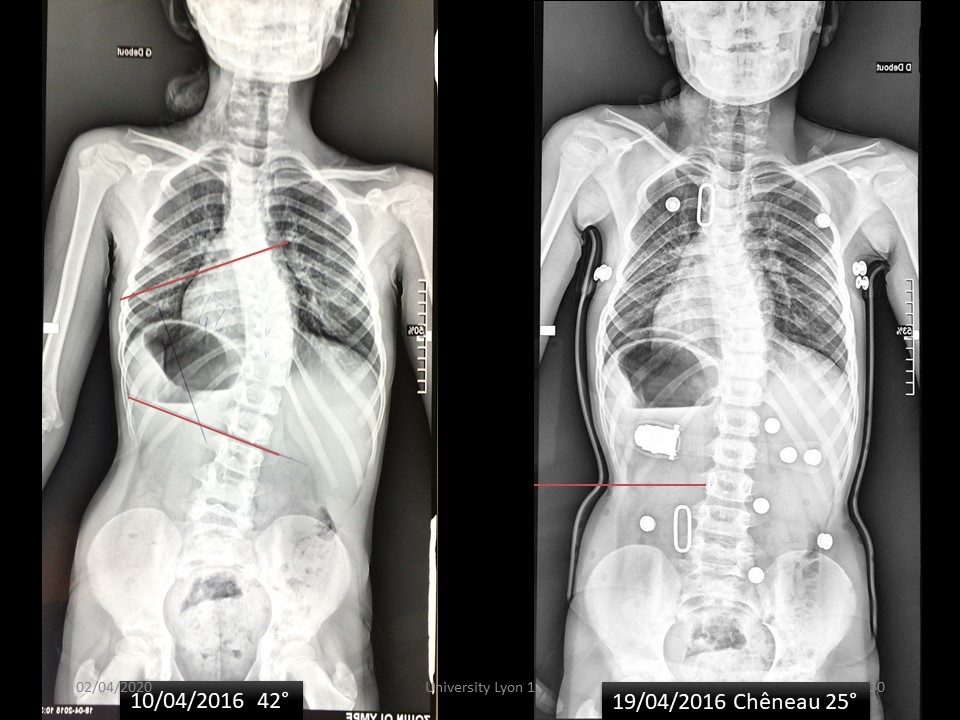

Oly scoliosis was discovered at the age of 2 years with an initial curvature of 30°. The first Milwaukee brace put in place was unsupported and a Chêneau brace by counter worn well for 3 years. Despite good compliance, the angulation progresses, and we see her at the age of 8 years with an angulation of 42°. |

|

Under the Chêneau brace, the angulation is reduced to 25°, essentially in the lower part of the scoliosis. |

The ARTbrace is much more corrective in both the frontal and sagittal planes. |

6 months after fitting, the angulation without brace is 17°. |